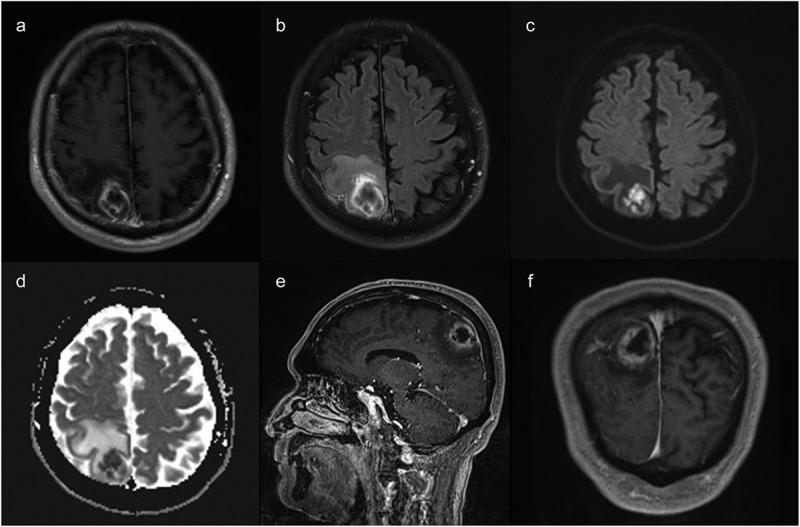

This case reports a 70-year-old male patient who developed an odontogenic brain abscess secondary to periodontal infection and underwent neurological surgery. Extract pus during surgery for the metagenomic next-generation sequencing (mNGS).

The mNGS of pus samples obtained from brain abscess aspiration identified the periodontal pathogens and . Consequently, he was referred to the department of stomatology for further examination and treatment.

本病例报告了一名70岁男性患者,因牙周感染继发牙源性脑脓肿并接受了神经外科手术。术中抽取脓液进行宏基因组下一代测序(mNGS)。

从脑脓肿穿刺抽取的脓液样本进行mNGS检测,鉴定出牙周病原体和。因此,他被转诊至口腔科进行进一步检查和治疗。